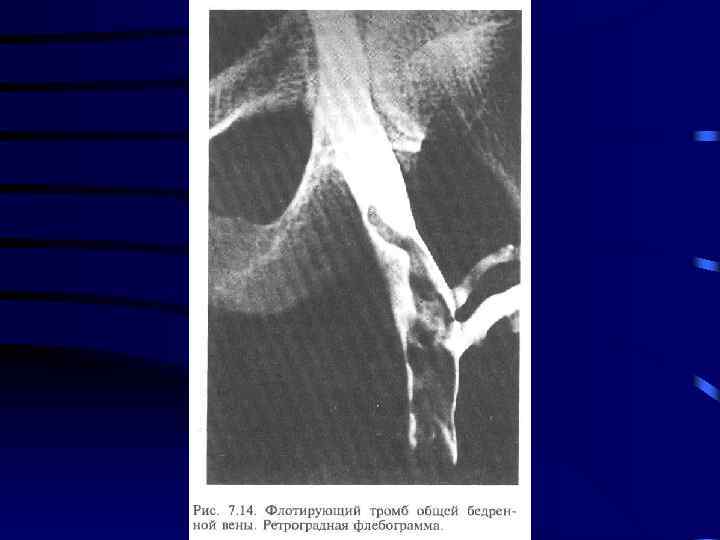

Диагностика: 1. Клиника 2. УЗИ сосудов 3. Дуплексное сканирование 4. Флебография

Лечение: 1. Консервативная терапия: a) Эластическое бинтование с возвышенным положением b) Гепарин c) Антибиотики d) Покой 5 -7 суток 2. При флотирующем или эмбологенном тромбозе хирургическое лечение: a) Установка Кава-Фильтра b) Пликация вен выше места тромба